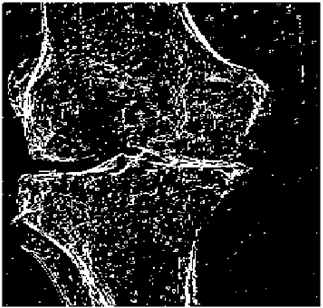

Table 10. Edge-detected image of “X-ray 1” after binarization for different noises.

NoiseCannyStandardSmooth

No noise Mathematics 10 02421 i072 Mathematics 10 02421 i073 Mathematics 10 02421 i074

G(0.001) Mathematics 10 02421 i075 Mathematics 10 02421 i076 Mathematics 10 02421 i077

G(0.002) Mathematics 10 02421 i078 Mathematics 10 02421 i079 Mathematics 10 02421 i080

G(0.003) Mathematics 10 02421 i081 Mathematics 10 02421 i082 Mathematics 10 02421 i083

I(0.25%) Mathematics 10 02421 i084 Mathematics 10 02421 i085 Mathematics 10 02421 i086

I(0.5%) Mathematics 10 02421 i087 Mathematics 10 02421 i088 Mathematics 10 02421 i089

I(1%) Mathematics 10 02421 i090 Mathematics 10 02421 i091 Mathematics 10 02421 i092

Table 10 shows the following:

• In all cases, the Canny edge detector detects more edge pixels than both fuzzy compositions.

• As the level of noise increases, Canny and standard composition become adversely affected by the noise, and still more edges are detected by Canny; however, most of the detected edges by Canny are misdetections due to the impact of noise. As is obvious from this table, the smooth composition provides a better image with reduced noise density.

• In all cases, the PFOM value for the smooth composition is always greater than the PFOM value for the standard composition, according to Table 6.